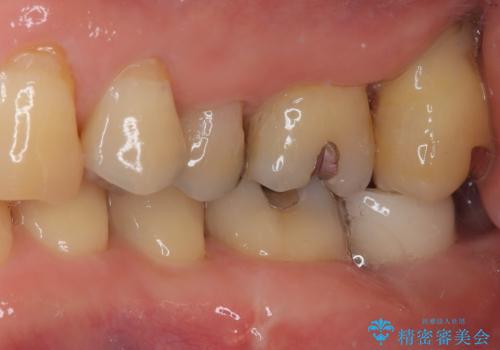

上顎の奥歯は、左右ともに外側に転位しており、特に右上はむし歯の範囲が広く、根管治療も必要な状態でした。

左下の奥歯は状態が非常に悪く、保存は困難と判断されたため、インプラントによる補綴治療が必要でした。

上顎左右の歯をアンカースクリューを用いた部分矯正により位置を修正し、オールセラミッククラウンにて補綴治療を行うこととしました。